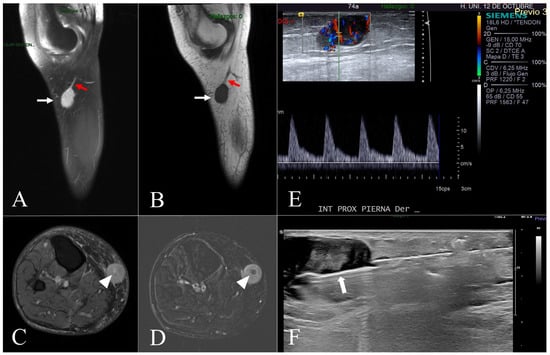

Malignant Tumours Presenting as Chronic Leg or Foot Ulcers

22 May 2021

Our purpose was to collect data on the incidence of malignant skin tumours presenting as chronic leg or foot ulcers in a tertiary centre, and to analyse the frequency and type of initial clinical misdiagnoses in these cases. A retrospective chart rev...